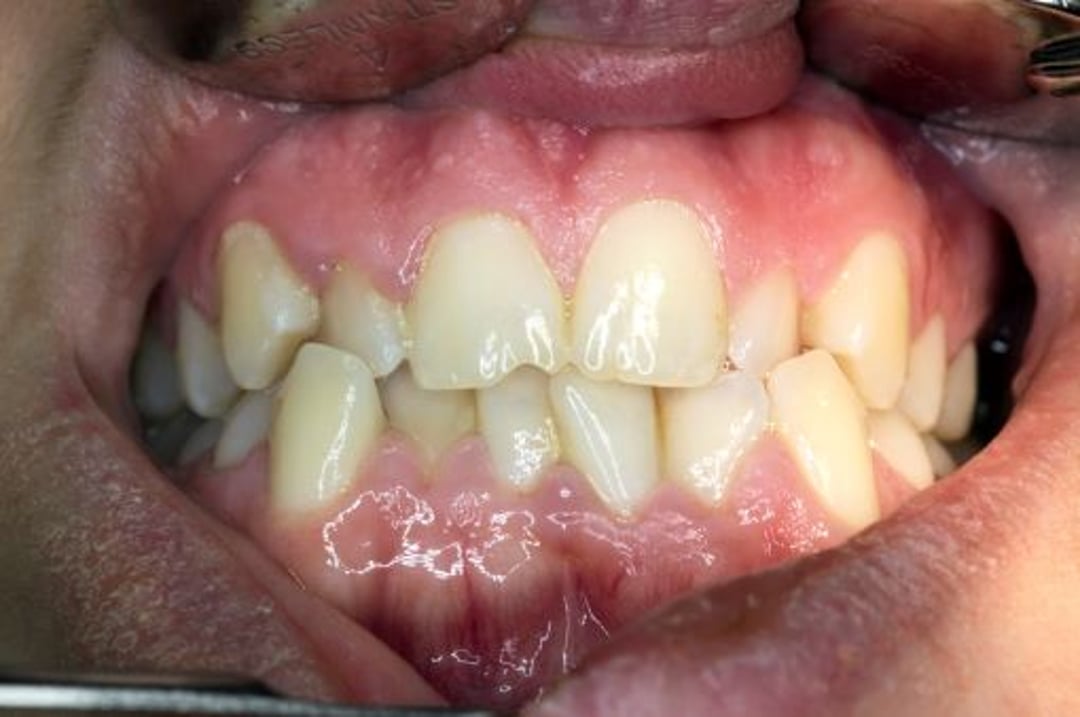

Fehlbiss

Die oberen und unteren Zähne sind fehlgerichtet, wenn der Kiefer geschlossen ist.

DR. ARMEN TARANYAN / SCIENCE PHOTO LIBRARY